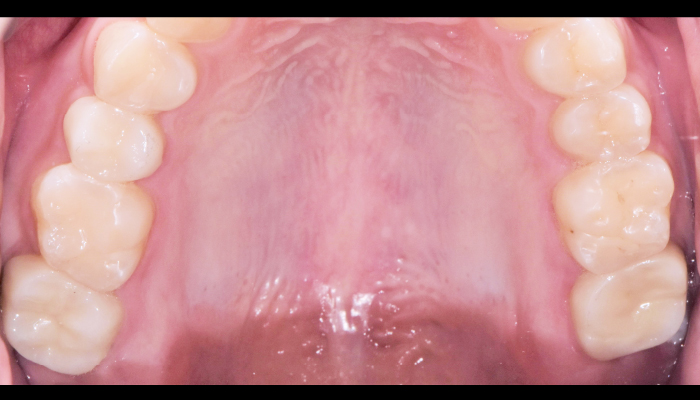

양쪽 아래 어금니 충치 치료

황OO님 전후사진 / 치료 기간 : 당일 / 레진, 인레이

양쪽 아래 어금니 충치 치료

황OO님 전후사진 / 치료 기간 : 당일 / 레진, 인레이

우측 위 어금니 충치 치료

임OO님 전후사진 / 치료 기간 : 당일 / 레진, 인레이

양쪽 아래 어금니 충치 치료

박OO님 전후사진 / 치료 기간 : 당일 / 레진, 인레이